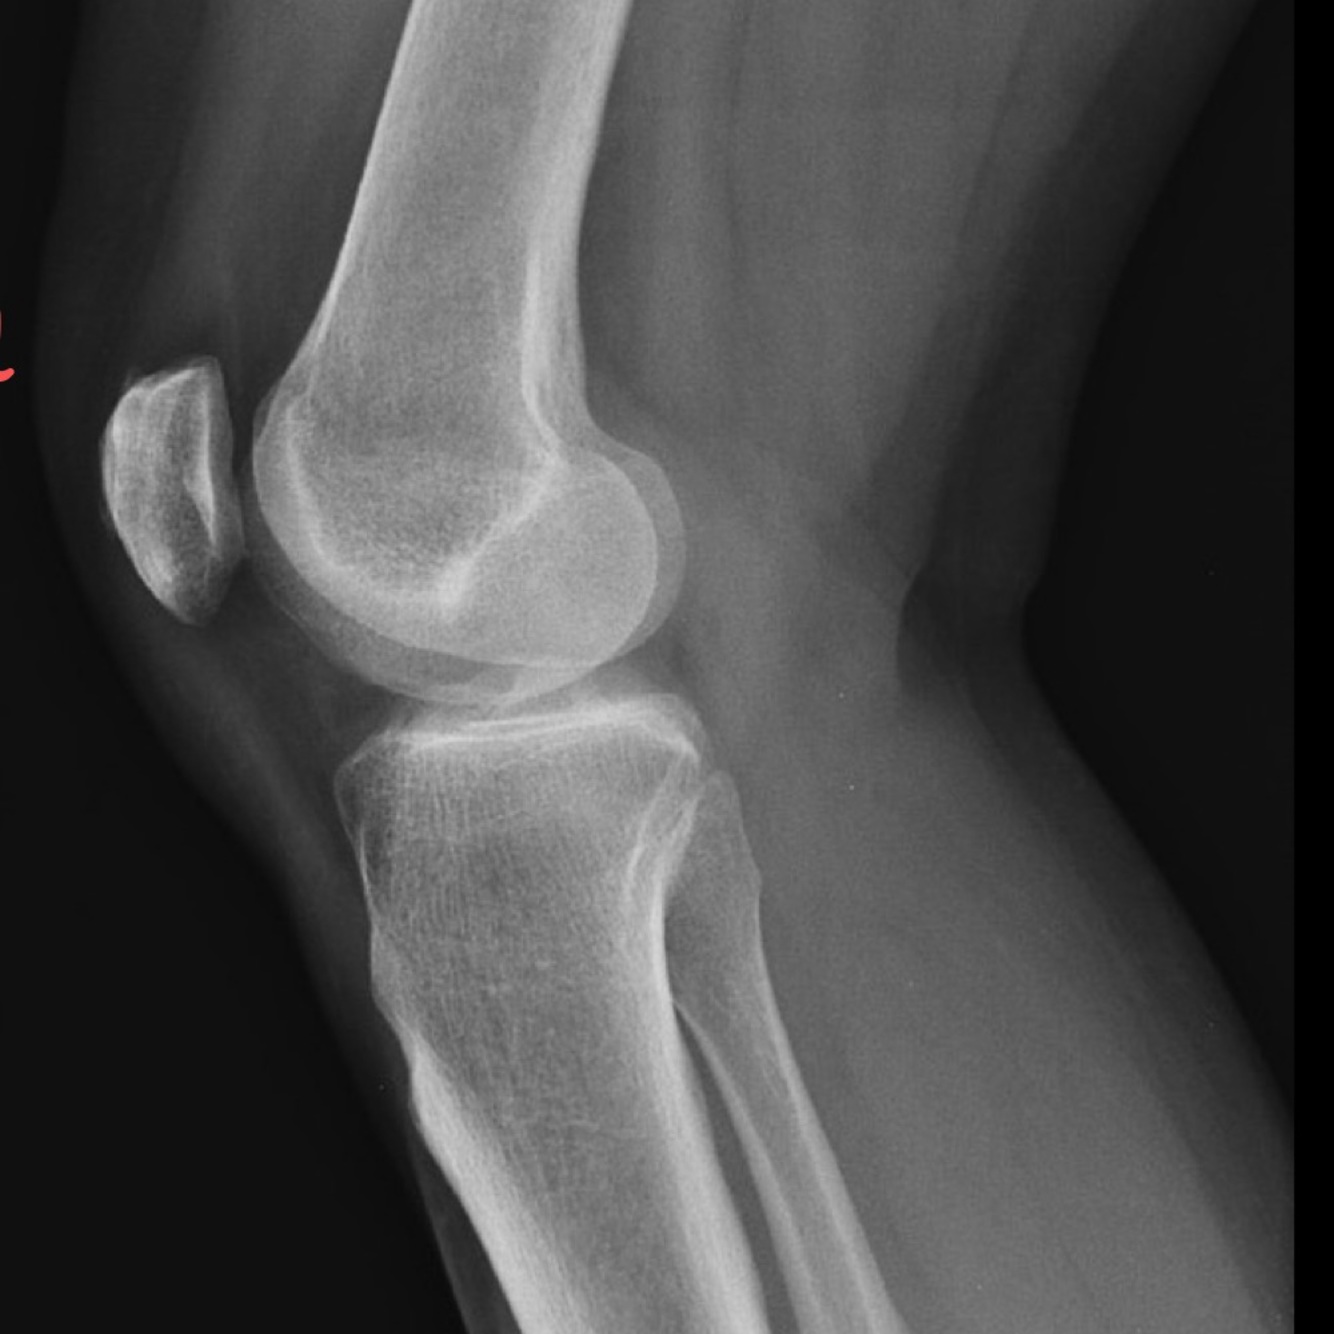

Q

Type de vue?

A

Tunellaire